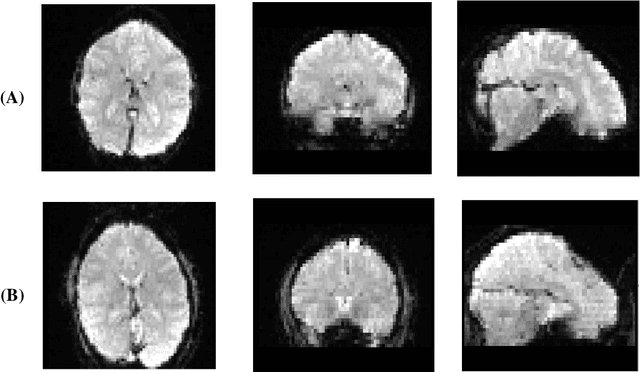

Abstract:Bipolar Disorder (BD) is a psychiatric condition diagnosed by repetitive cycles of hypomania and depression. Since diagnosing BD relies on subjective behavioral assessments over a long period, a solid diagnosis based on objective criteria is not straightforward. The current study responded to the described obstacle by proposing a hybrid GAN-CNN model to diagnose BD from 3-D structural MRI Images (sMRI). The novelty of this study stems from diagnosing BD from sMRI samples rather than conventional datasets such as functional MRI (fMRI), electroencephalography (EEG), and behavioral symptoms while removing the data insufficiency usually encountered when dealing with sMRI samples. The impact of various augmentation ratios is also tested using 5-fold cross-validation. Based on the results, this study obtains an accuracy rate of 75.8%, a sensitivity of 60.3%, and a specificity of 82.5%, which are 3-5% higher than prior work while utilizing less than 6% sample counts. Next, it is demonstrated that a 2- D layer-based GAN generator can effectively reproduce complex 3D brain samples, a more straightforward technique than manual image processing. Lastly, the optimum augmentation threshold for the current study using 172 sMRI samples is 50%, showing the applicability of the described method for larger sMRI datasets. In conclusion, it is established that data augmentation using GAN improves the accuracy of the CNN classifier using sMRI samples, thus developing more reliable decision support systems to assist practitioners in identifying BD patients more reliably and in a shorter period